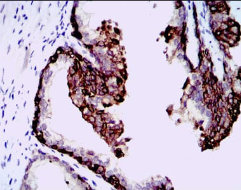

HAS3 Mouse Monoclonal antibody[3C9B2]

Species Reactivity:    Human

IHC    1/200 - 1/1000